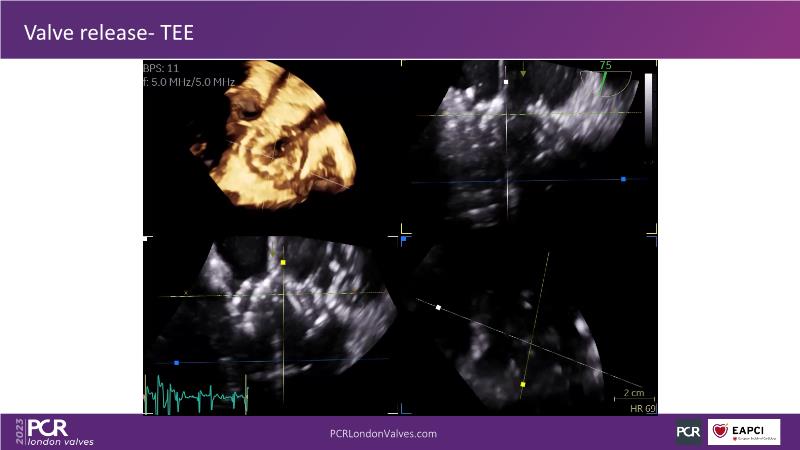

This session explores the features of the PASCAL Precision and the EVOQUE tricuspid replacement systems through simulators and case presentations, while a panel of experts discuss the technology, witnessing live demonstrations of treating mitral and tricuspid regurgitation patients.

- To learn about the differentiating features of the PASCAL Precision system showcased in a series of simulators alongside case presentations

- To interact with a panel of experts discussing the PASCAL Precision system technology and showcasing, live, its different key features in action and how they help treat mitral regurgitation and tricuspid regurgitation patients

- To introduce the EVOQUE tricuspid replacement system showcased with a simulator and a case presentation